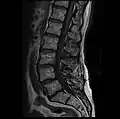

MRI lumbar spine post-hemilaminectomy (sagittal T2 FRFSE)

-

MRI lumbar spine post-hemilaminectomy (sagittal T1 FSE)